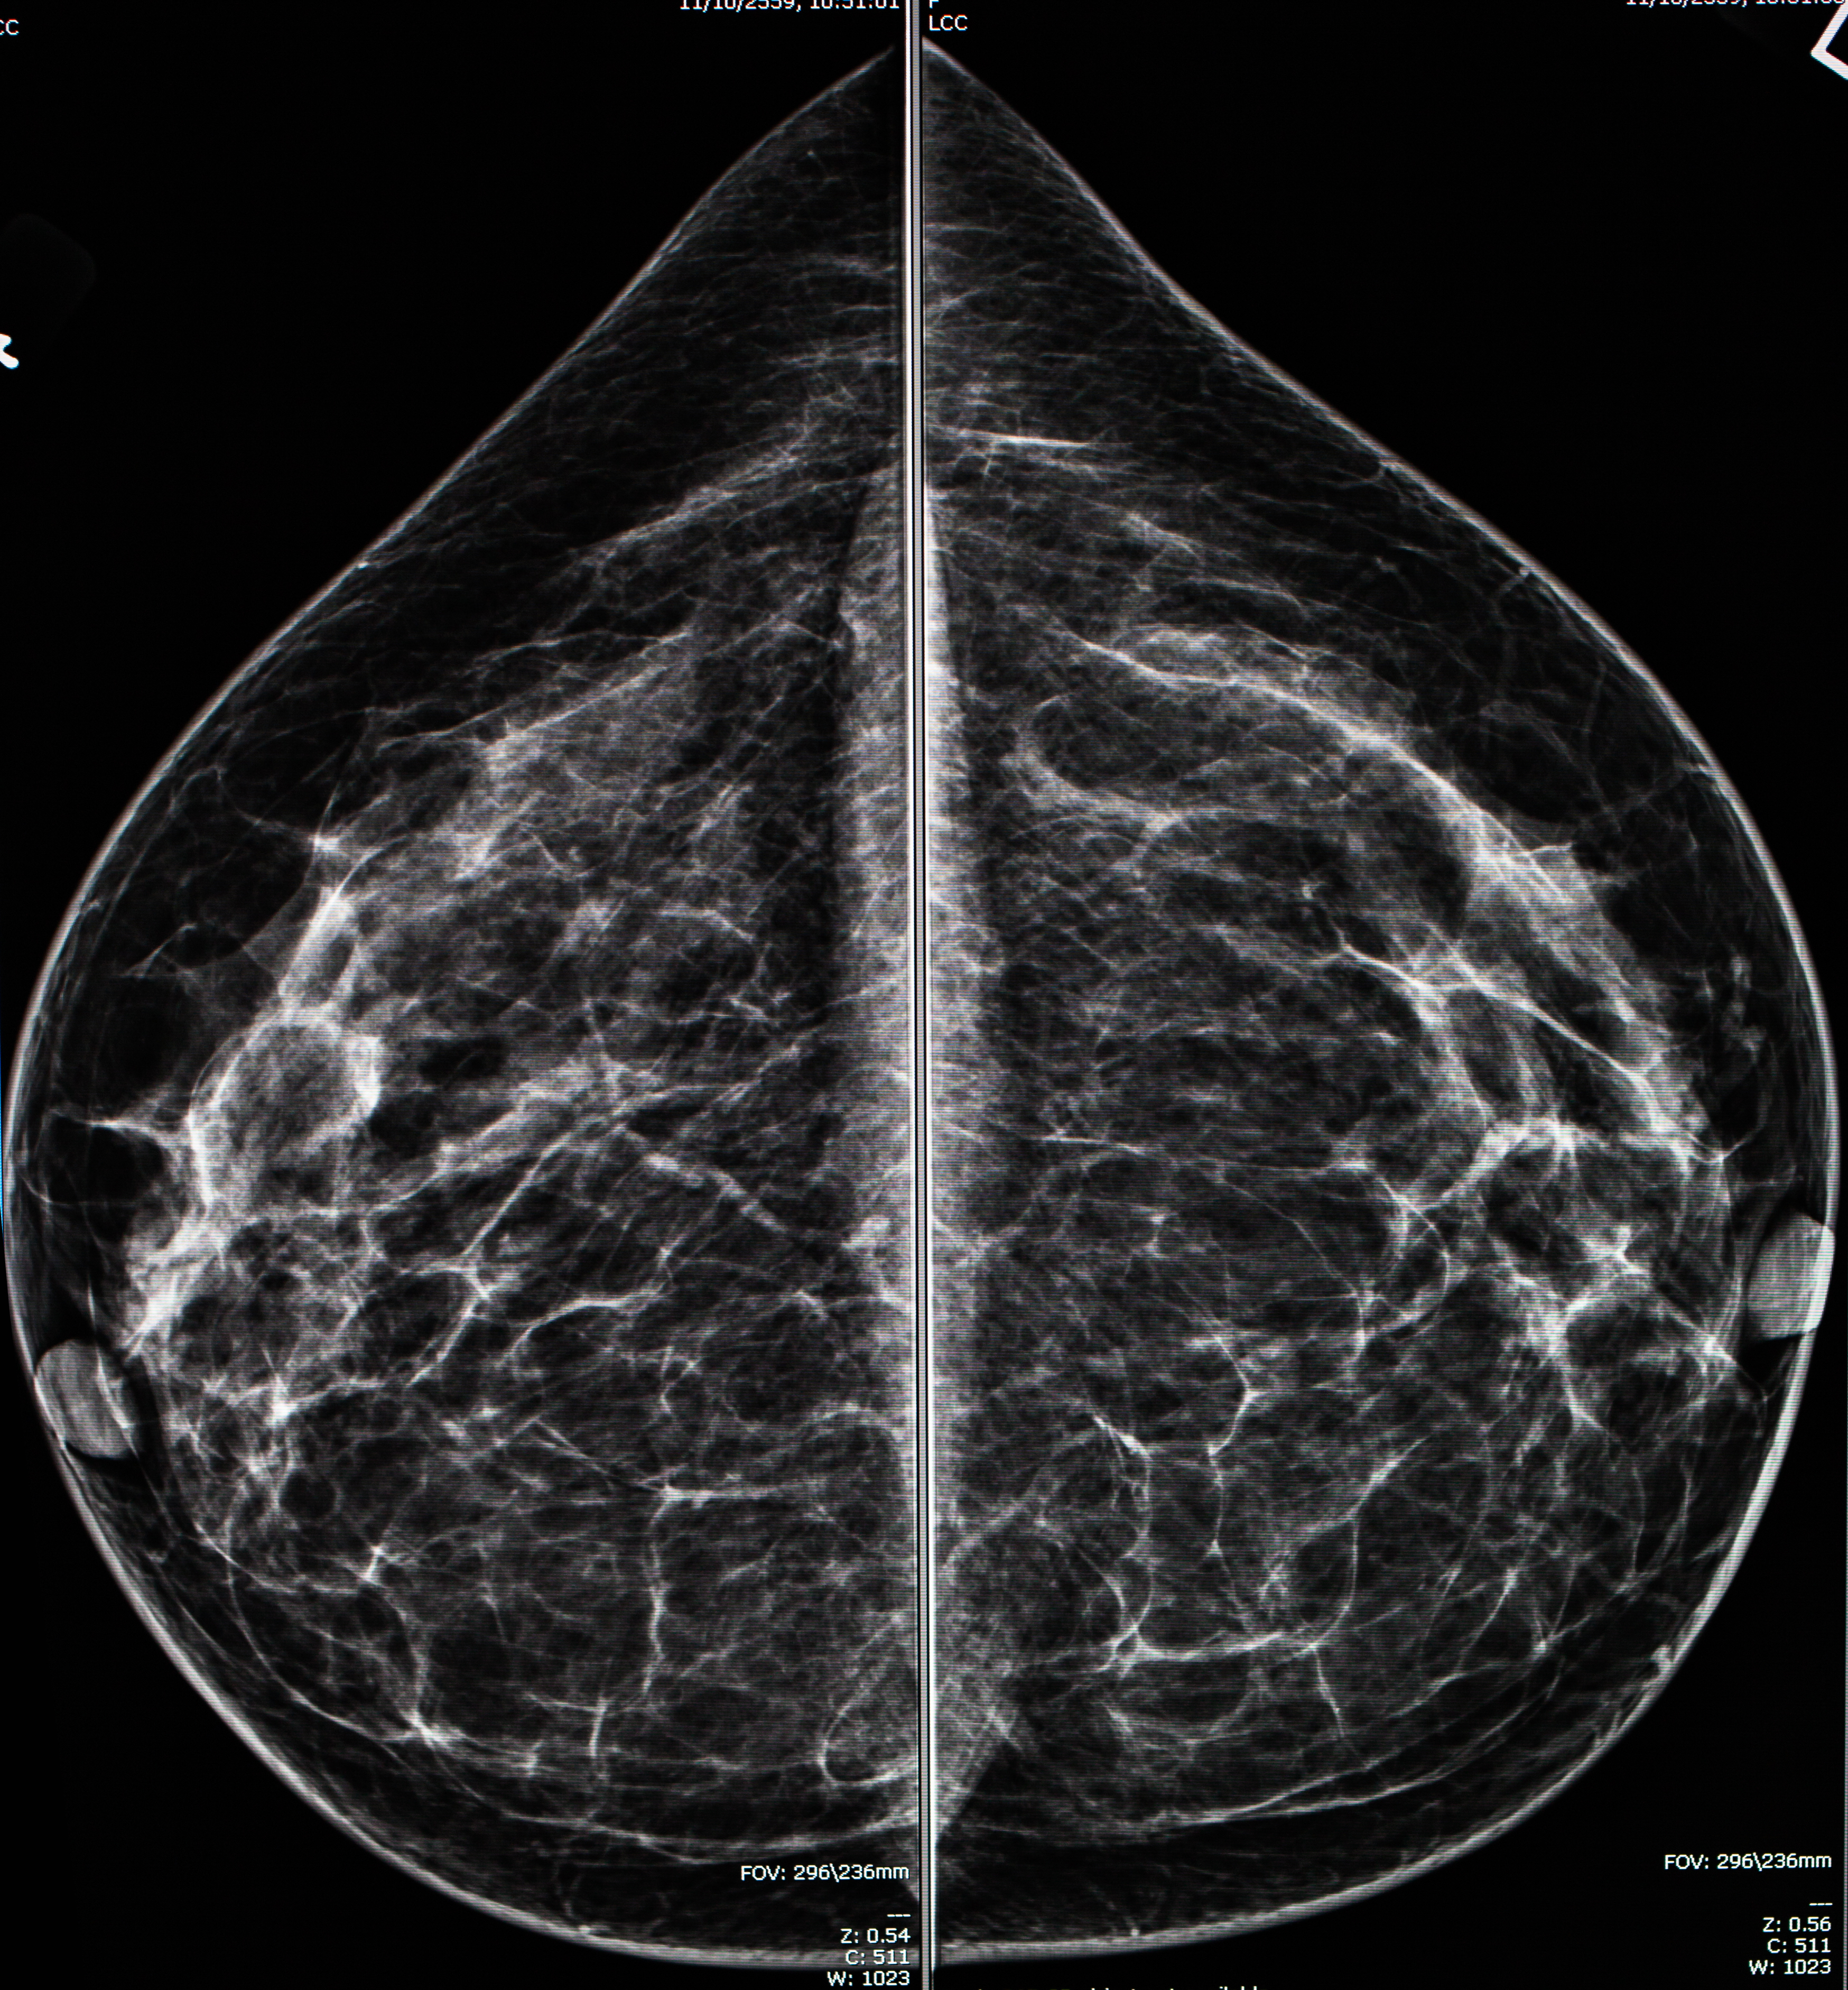

이것이 일반적인 유방촬영술의 결과물입니다. 어느 병원에서 찍든 두가지 방법의 이미지를 얻고, 방향은 정해져 있습니다. 각각 알아볼까요?

이 이미지는 오른쪽(R), 왼쪽(L) CC(craniocaudal) view입니다. 쉽게 말해 유방을 위아래로 눌러 찍은 영상입니다. 이 영상에서는 내측 유방이 잘 포함되어야 하고 외측도 최대한 포함 되게 찍습니다. 영상의 위가 유방의 바깥쪽, 아래가 유방의 안쪽입니다.

이 이미지는 오른쪽(R), 왼쪽(L) MLO(mediolateral oblique) view 입니다. 이는 유방을 안쪽 바깥쪽으로 압력을 주는데, 약간 비스듬히 압박 하는 방법입니다. 이 방법은 단일 촬영으로 가장 많은 유방조직을 보여줄 수 있습니다. 영상의 위가 유방의 위쪽, 아래가 유방의 아래쪽 입니다.